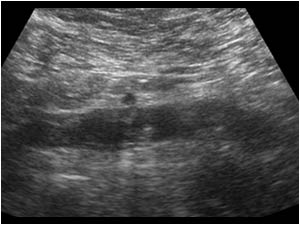

Huyết khối TM chủ dưới

Huyết khối TM chủ dưới - Ảnh 2

» Thông tin: Nữ giới – 68 tuổi.

» Lâm sàng: Sưng phù chi dưới.